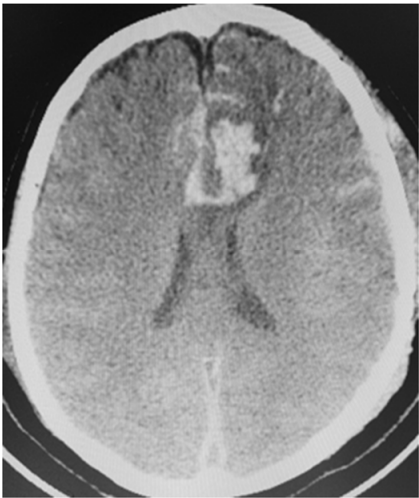

Uma paciente de 66 anos de idade, tabagista, hipertensa com tratamento irregular. Apresentou cefaleia súbita de severa intensidade associada a náuseas. Ao exame físico, observaramse AC = RR2T com BNF, FC = 100 bpm, AP = MVF sem RA, FR = 15 irpm, PA = 182 mmHg x 100 mmHg, SatO2 em ar ambiente = 97%, Glasgow 15, pupilas isofotorreagentes, sem deficits focais. TC crânio e arteriografia a seguir.

Fonte: Acervo pessoal.

Acerca desse caso clínico e com base nos conhecimentos médicos correlatos, julgue os itens a seguir.

O risco de ruptura transoperatória do aneurisma roto da paciente é maior em uma cirurgia tardia quando comparado com a cirurgia precoce.

Apenas um dos aneurismas evidenciados na angiografia pode ser acessado pelo acesso pterional.